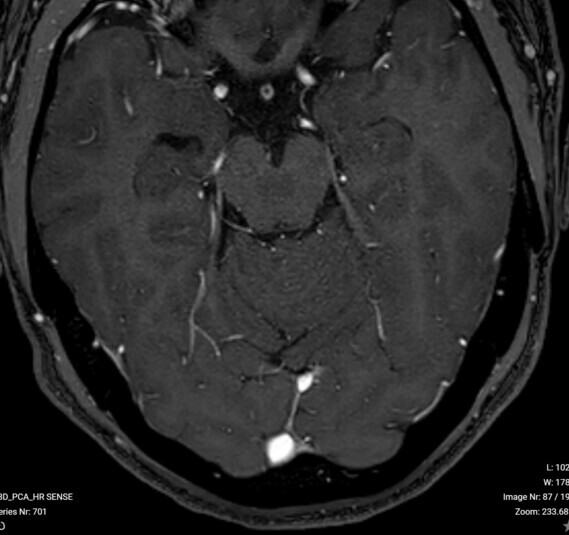

Que signifient les taches blanches sur l’image IRM ? Les points blancs que l’on voit sur les images IRM représentent du liquide. Dans le cas d’une IRM de la tête, les points blancs doivent donc être interprétés comme du liquide céphalo-rachidien (LCR).

Les modifications typiques de la SEP (“taches blanches”) représentent des foyers de forme arrondie et ovale, principalement disposés autour des ventricules cérébraux (périventriculaires), mais pouvant également affecter la jonction entre le tronc cérébral et le cervelet, ainsi que la partie supérieure de la moelle épinière (Les antidepresseurs augmentent les risques d hemorragies cerebrales).

Lorsque le tissu cérébral est endommagé – par exemple après un accident vasculaire cérébral, un traumatisme crânien, une inflammation ou encore des maladies comme la maladie d’Alzheimer ou la sclérose en plaques – une multiplication des cellules gliales de soutien est stimulée (taches blanches cerveau neurologique).